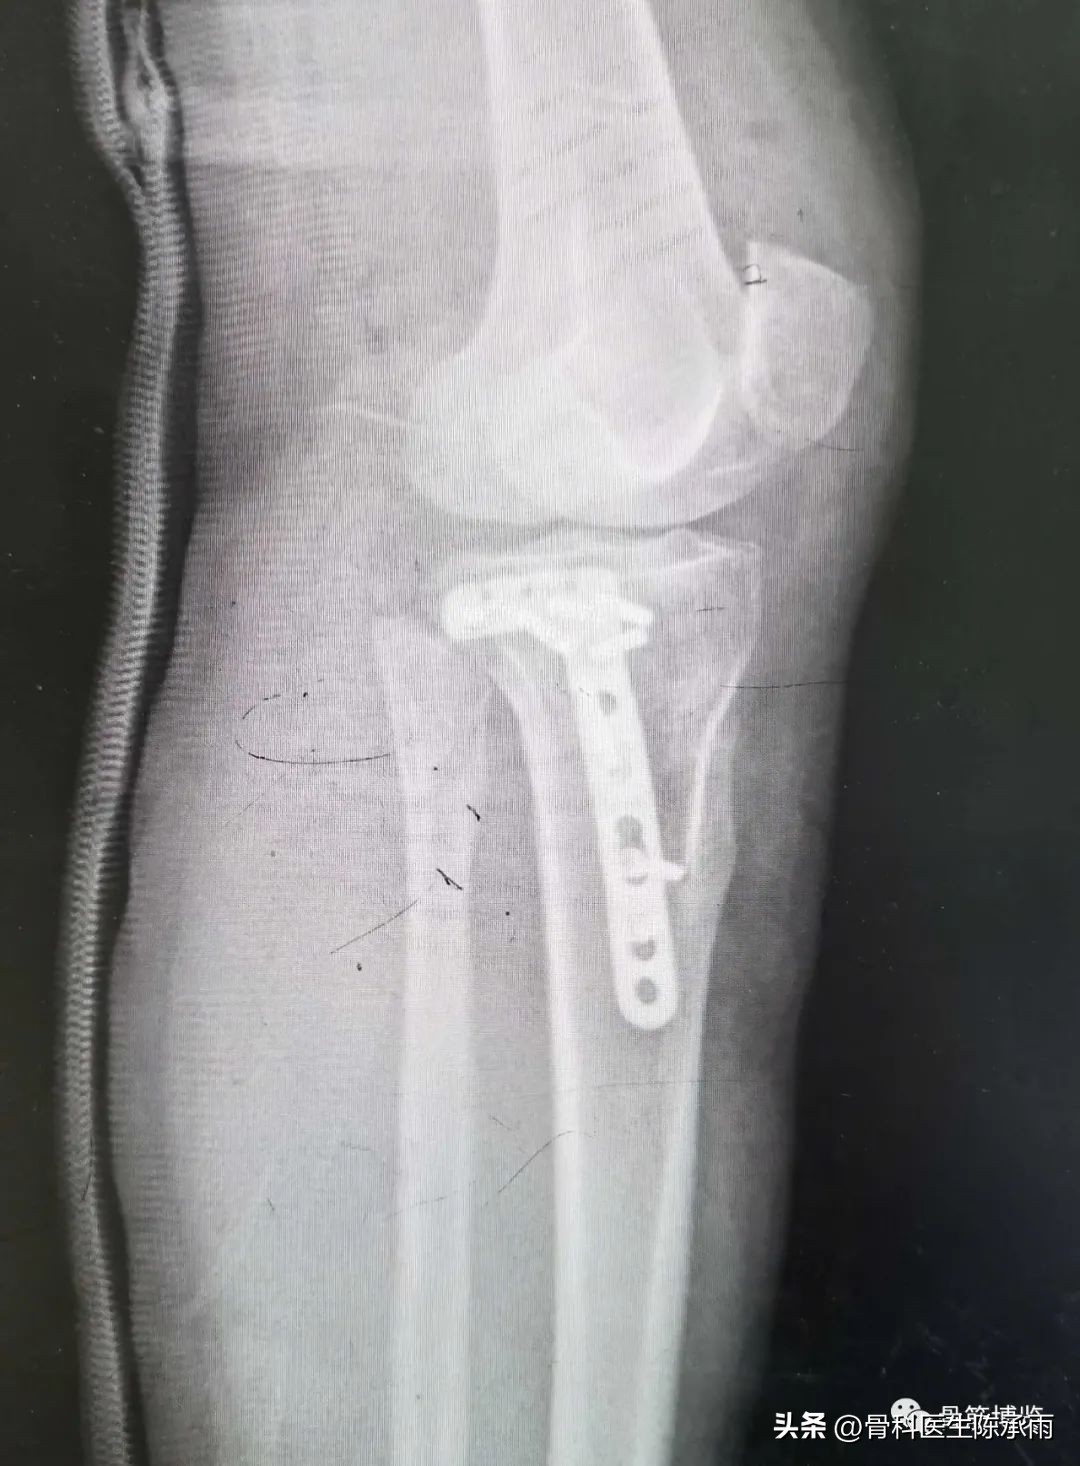

近段时间的胫骨平台骨折,没来得及详细整理

胫骨平台骨折的分型比较多,我们临床上常用的就是Schatzker分型和AO骨折的分型,还有骨折脱位的Hohi-Moore分型,这是我们常用的三个分型。

对AO 分型来讲,现在这是AO推出来更详细的,再分为ABC。随着分型的增加,从A到C骨折的损伤程度是越来越重,治疗也越来越困难,从1到2 ,123也是这个规律,骨折的分型就是给我们表明了骨折的一个损伤的程度,治疗办法和损伤的特点。我们对于骨折脱位的分型,常用Hohi-Moore分型,这个是弥补了,Schatzker和AO分型的一些缺陷。